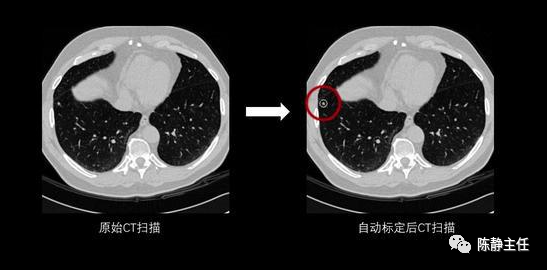

而且吃的好、却消化不了,所以郁堵结节的人,特别多,时代病。各种结节,甲状腺结节、淋巴结节、乳腺结节,2个中药通治,太强大了。2个鲜为人知的好药: 理气化痰、活血化瘀、软坚散结,对各类结节有效。

第二是甲状腺结节、增生: